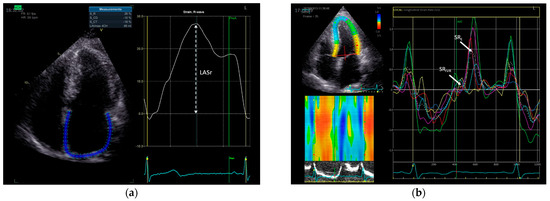

2.2. Echocardiography

| LASr, % SRIVR, s–1 SRE, s–1 | 24 (21–26) 0.27 (0.19–0.37) 0.89 (0.80–1.23) | 21 (17–24) 0.28 (0.21–0.44) 1.00 (0.73–1.31) | 0.046 0.62 0.69 |